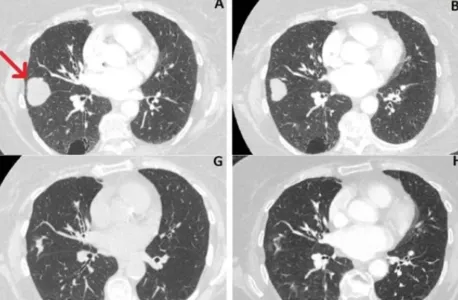

Autor Imagens do exame mostram que tumor diminuiu de cerca de 41 mm para 10 mm - Foto: Metrópoles

Imagens de exames mostram que o tamanho do tumor diminuiu de 41 mm, em junho de 2018, para 10mm, em março de 2021. Ou seja, uma redução de cerca de 76%.